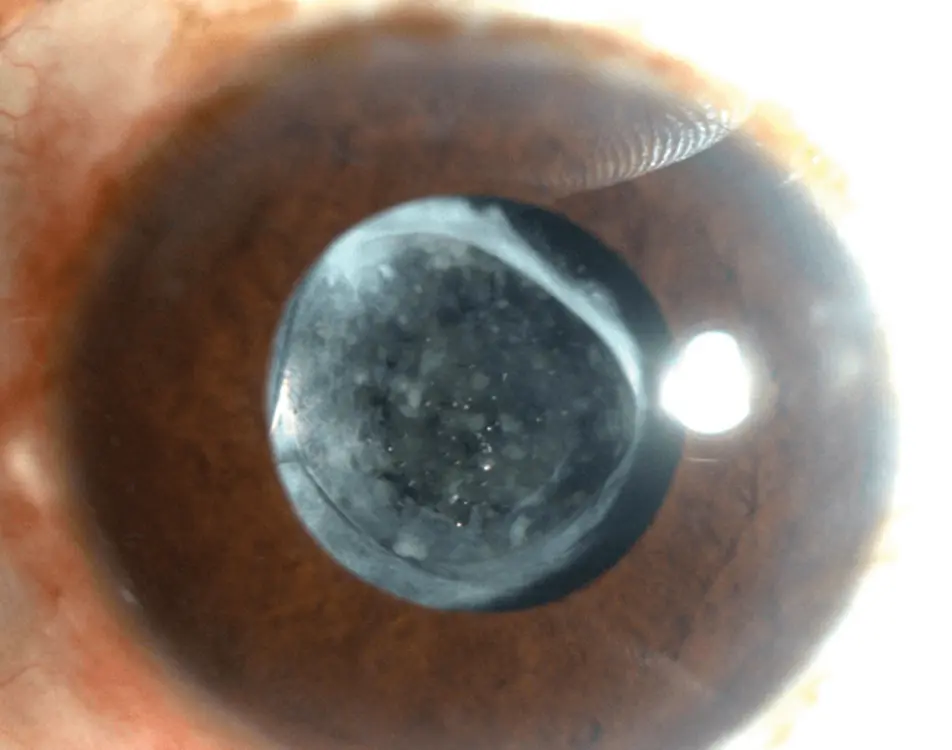

Con el tiempo, algunos pacientes pueden experimentar una reducción progresiva de la agudeza visual. Esto se debe a la opacificación de la cápsula, conocida como “opacidad capsular posterior”.

Este tipo de opacidad se trata de forma rápida, ambulatoria y no invasiva mediante un procedimiento llamado capsulotomía posterior con láser, que consiste en crear una apertura central en la cápsula posterior utilizando pulsos de láser de alta energía, sin necesidad de realizar cortes ni incisiones quirúrgicas, restaurando así la transparencia del eje visual.

ANTES